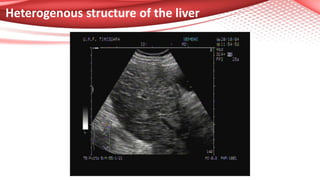

Heterogenous structure of the liver

US evaluation of the liver structure

Usually, normal liver texture is homogenous, with hepatic and

portal veins very well seen;

In pathological conditions, we look for steatosis (“bright liver”

with posterior attenuation) or for advanced fibrosis

(inhomogeneous liver, irregular surface, signs of portal

hypertension, size of caudate lobe).